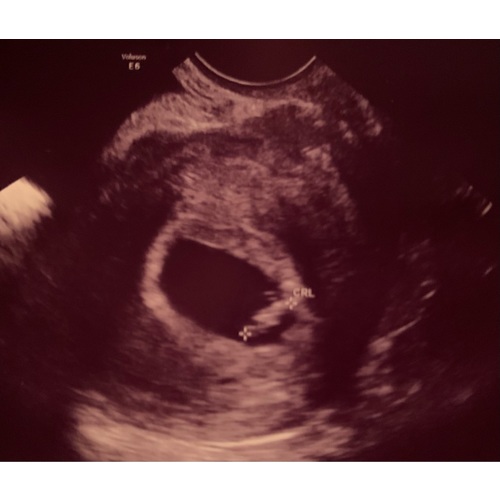

Dit was op 7+1 Maar het ziet er bij iedereen beetje anders uit dus staar je niet blind op andere echo's... Probeer te genieten en kwens je een vlotte zwangerschap❤